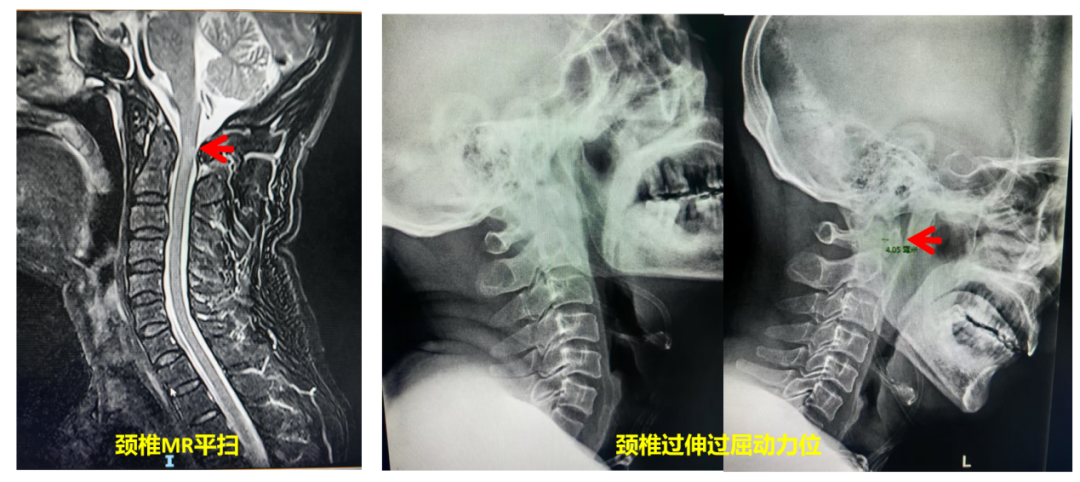

直到最近一次晕厥摔倒后,王先生出现了四肢麻木乏力的症状,为诊断提供了关键线索。王先生在朋友介绍下来到了广州医科大学附属第二医院(简称:广医二院)脊柱外科就诊,经验丰富的任辉博士敏锐地捕捉到这一变化,并通过颈椎过伸过屈位动态检查,最终揭示真相:王先生的晕厥根源是寰枢椎不稳(第1颈椎与第2颈椎之间的关节不稳定),此次外伤后颈髓挫伤也更明确了责任节段。

“动态评估是关键的一步,医生通常会通过颈椎过伸过屈位X光或MRI进行动态评估,捕捉常规体位下难以发现的异常活动直接观察脊髓是否在特定位置受到撞击或压迫。”江晓兵指出,必要时还需要结合其他检查手段如CT、CTA等对骨骼结构与血管的复杂关系进行综合研判。正是医生基于经验的层层推理和检查手段的精准组合,才能最终让这个“隐匿的杀手”无处遁形。